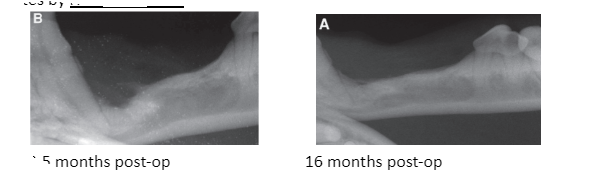

JVD 2014, Honzelka, Modified Conservative Treatment of an Extensive Dentigerous Cyst in a Dog, which of the following is true?

a) DTC originates from the remaining enamel organ or reduced enamel epithelium that surrounds the crown during odontogenesis

and attaches to the tooth at the cementoenamel junction

JVD 2014, Honzelka, Modified Conservative Treatment of an Extensive Dentigerous Cyst in a Dog, which of the following treatment options was pursued?

c) Subtotal cystic lining debridement and extraction